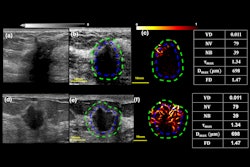

The study included 334 breast lesions, of which 183 were masses and 151 were nonmass lesions. Histological analysis revealed 257 benign lesions and 77 malignant lesions.

While sensitivity remained high with or without AI assistance, combining AI assistance with radiologist interpretation significantly increased specificity compared with unassisted interpretation by radiologists (p < 0.001).

Impact of AI’s performance on targeted breast ultrasound interpretation | |||

Measure | Radiologist alone | AI alone | AI + radiologist |

Sensitivity | 100% | 100% | 100% |

Specificity | 12.8% | 19.5% | 28% |

Positive predictive value | 25.6% | 27.1% | 29.4% |

Negative predictive value | 100% | 100% | 100% |

Accuracy | 32.9% | 38% | 44.6% |

The team also found that all lesions classified as BI-RADS 2 or 3 on targeted ultrasound by the radiologist or the AI software (n = 72, 21.6% of 334) showed benign pathology results.